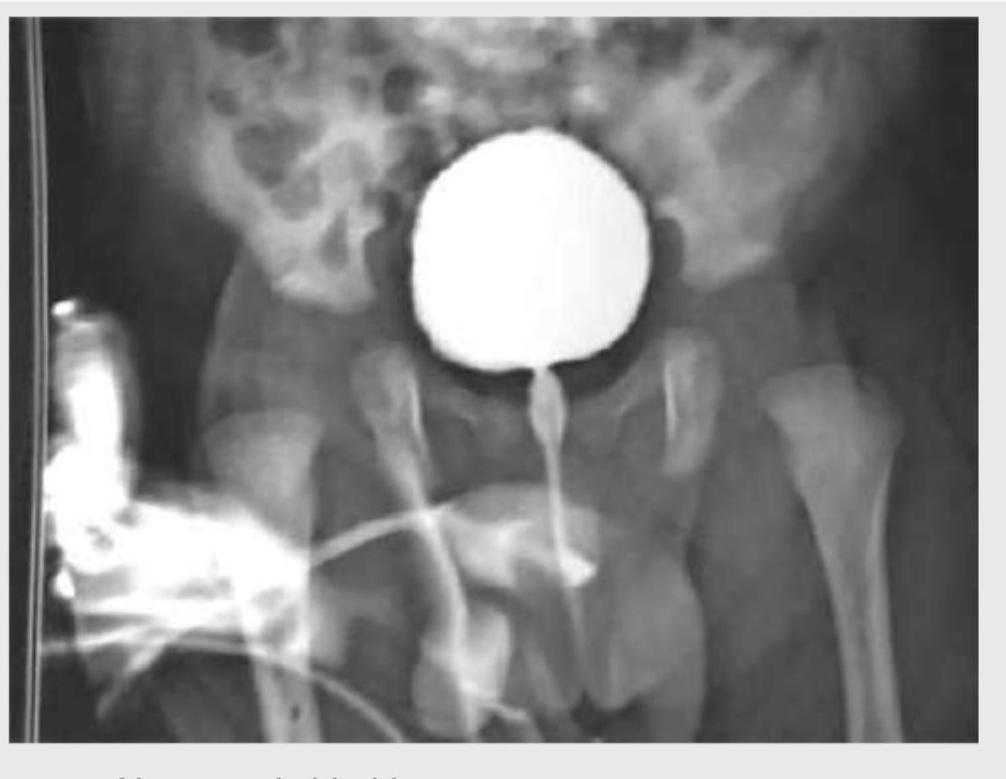

After her first urinary tract infection (UTI), a 1-year-old girl has a voiding cystourethrogram with findings shown below. Which of the following is the most appropriate management option?

Explanation: ***Low-dose daily antibiotics*** - **Prophylactic antibiotics** are the first-line conservative management for **Grade II-III vesicoureteral reflux (VUR)** in young children to prevent recurrent UTIs and potential **renal scarring**. - This approach allows time for potential **spontaneous resolution** of VUR as the child grows, which commonly occurs in low-to-moderate grade reflux. *Immediate surgical reimplantation of the ureters* - **Ureteral reimplantation** is reserved for **high-grade VUR (Grade IV-V)** or cases with breakthrough infections despite prophylactic antibiotics. - **Grade II-III VUR** often resolves spontaneously with conservative management, making immediate surgery unnecessarily aggressive. *Weekly urinalyses and culture* - **Monitoring alone** without prophylaxis increases the risk of **recurrent UTIs** and potential **renal scarring** in a child with established VUR. - This approach fails to provide **active protection** against ascending infections that VUR predisposes the patient to. *Diet low in protein* - **Protein restriction** is indicated for **chronic kidney disease** with significant **renal impairment**, not for VUR management. - VUR with normal renal function does not require **dietary modifications**, and protein is essential for normal growth in children.